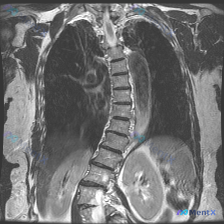

这张胸腰椎MRI冠状位,最突出的影像表现是什么?

影像显示胸腰段脊柱在冠状面上偏离中心垂线,形成以胸腰段交界处为顶点的向左侧凸畸形;椎体序列非线性,椎体形态尚完整;部分胸腰段及腰椎间盘T2信号不均匀减低;凹侧椎间隙略窄,凸侧相对较宽;椎管走行随侧弯弯曲,脑脊液信号相对连续;胸腔腹腔内脏器未见明显异常高信号或占位。